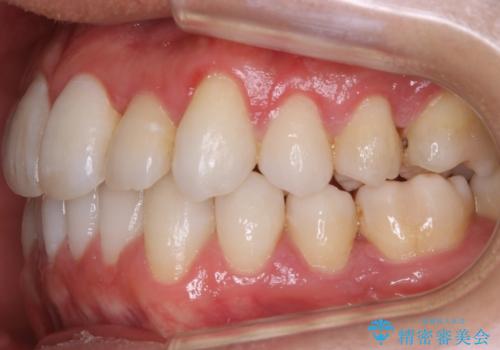

抜歯をせずとも笑った時の歯の見え方が劇的に変化していることが分かります。